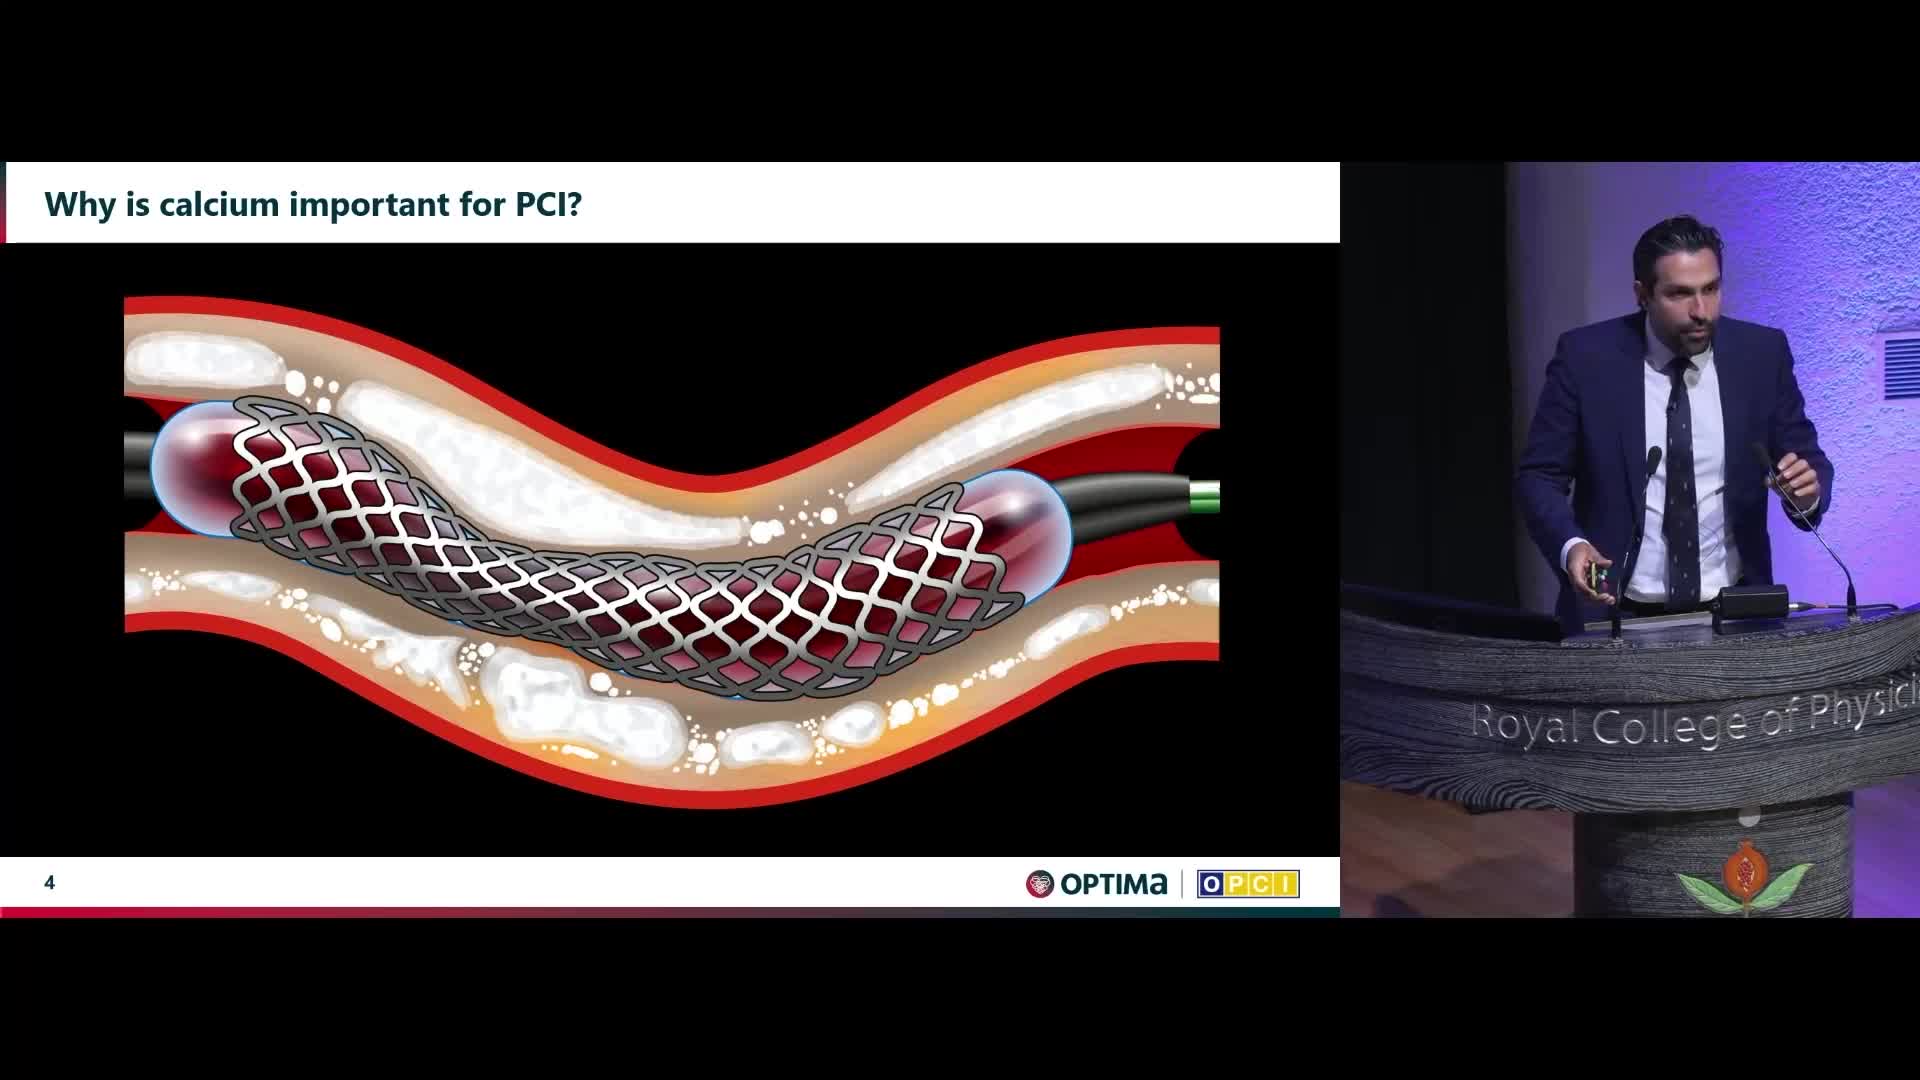

Session 2: Coronary calcium – too hard to crack?

Treatment of coronary arterial calcium (CAC) has being redefined. We explore the interaction between CAC and patient...